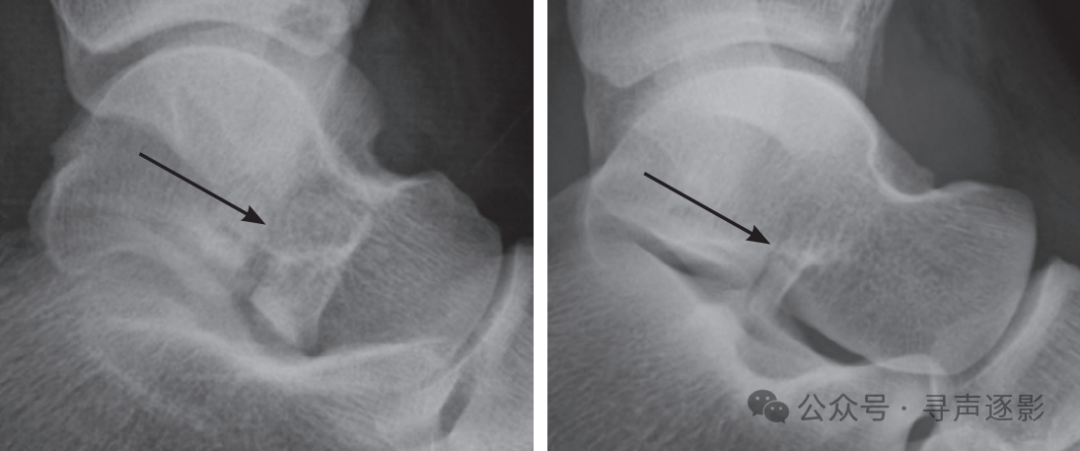

关节内骨折(箭头所示)累及距下关节(左图)或跟骰关节(右图)。

Bohler 角变平是侧位 X 线片所示跟骨骨折的主要征象。